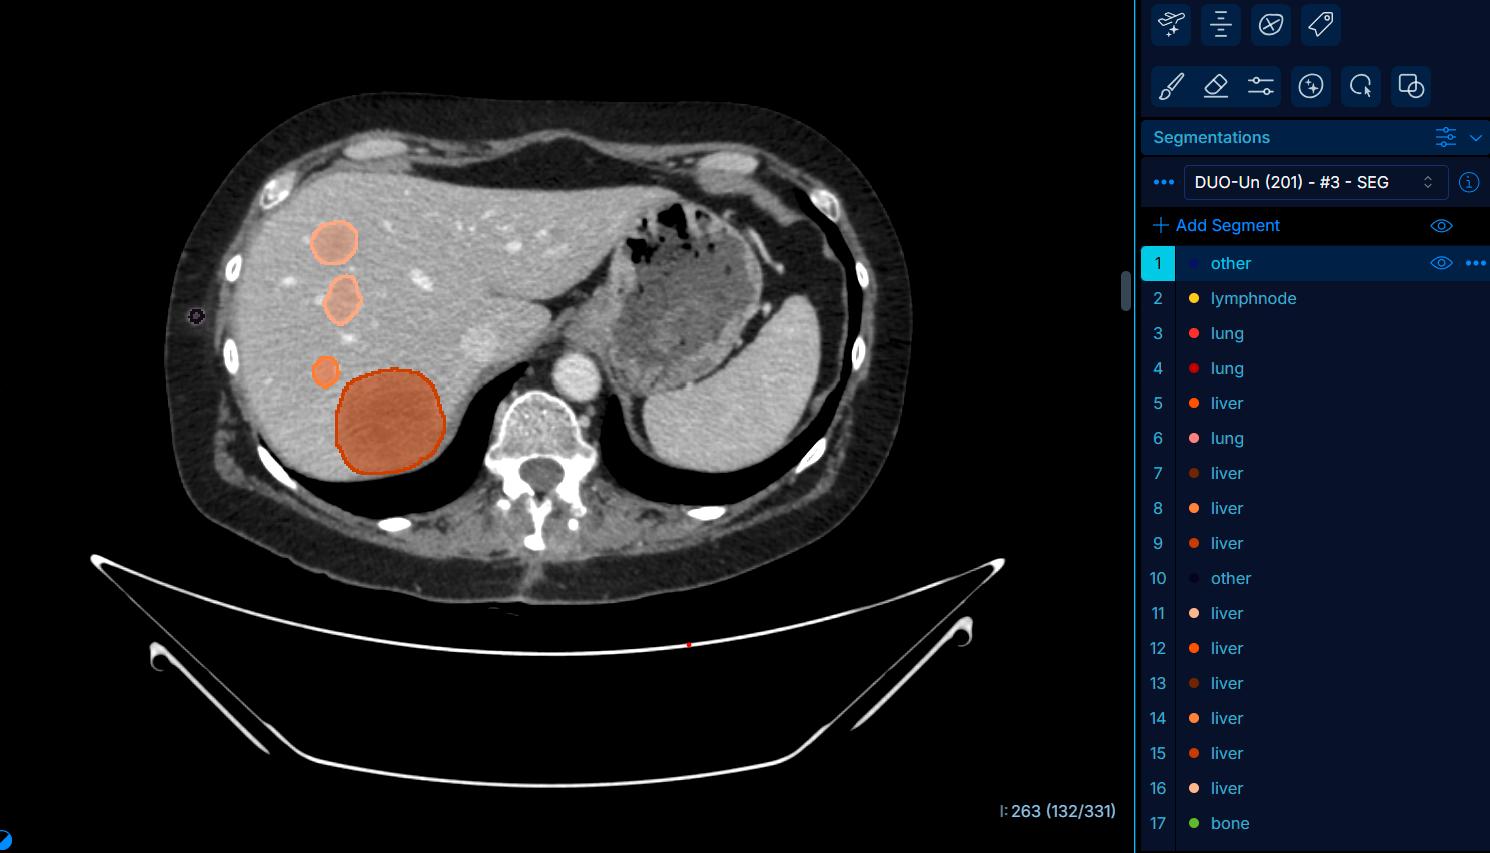

Un consortium français a développé DuOnco Unity, un outil d’intelligence artificielle capable d’analyser en 3D l’ensemble des lésions cancéreuses à partir d’un scanner. Cette innovation promet une évaluation plus précise de la charge tumorale, un gain de temps pour les praticiens et un suivi plus efficace de la maladie.

Grâce à un algorithme d’intelligence artificielle entraîné sur près de 287 000 lésions annotées, cet outil est capable de détecter automatiquement, en trois dimensions, toutes les tumeurs et métastases visibles sur un scanner. © Gustave-Roussy

La promesse d'un suivi plus rapide et précis des patients atteints de cancer. Le centre de lutte contre le cancer Gustave-Roussy (Villejuif, 94), le CHU d’Angers, le laboratoire Guerbet et l'entreprise Intrasense ont développé ensemble un outil d’intelligence artificielle capable d’analyser de manière exhaustive les lésions cancéreuses sur des examens de scanner thoraco-abdomino-pelvien. Baptisé DuOnco Unity®, il est présenté dans un communiqué diffusé le 7 avril par Gustave-Roussy.

Aujourd’hui, l’évaluation de l’efficacité des traitements anticancéreux repose principalement sur les critères RECIST, un standard basé sur la mesure d’un nombre limité de lésions dites « cibles », rappelle le communiqué. Si cette méthode a fait ses preuves, elle présente toutefois des limites importantes, notamment chez les patients avec un grand nombre de métastases réparties sur plusieurs organes.